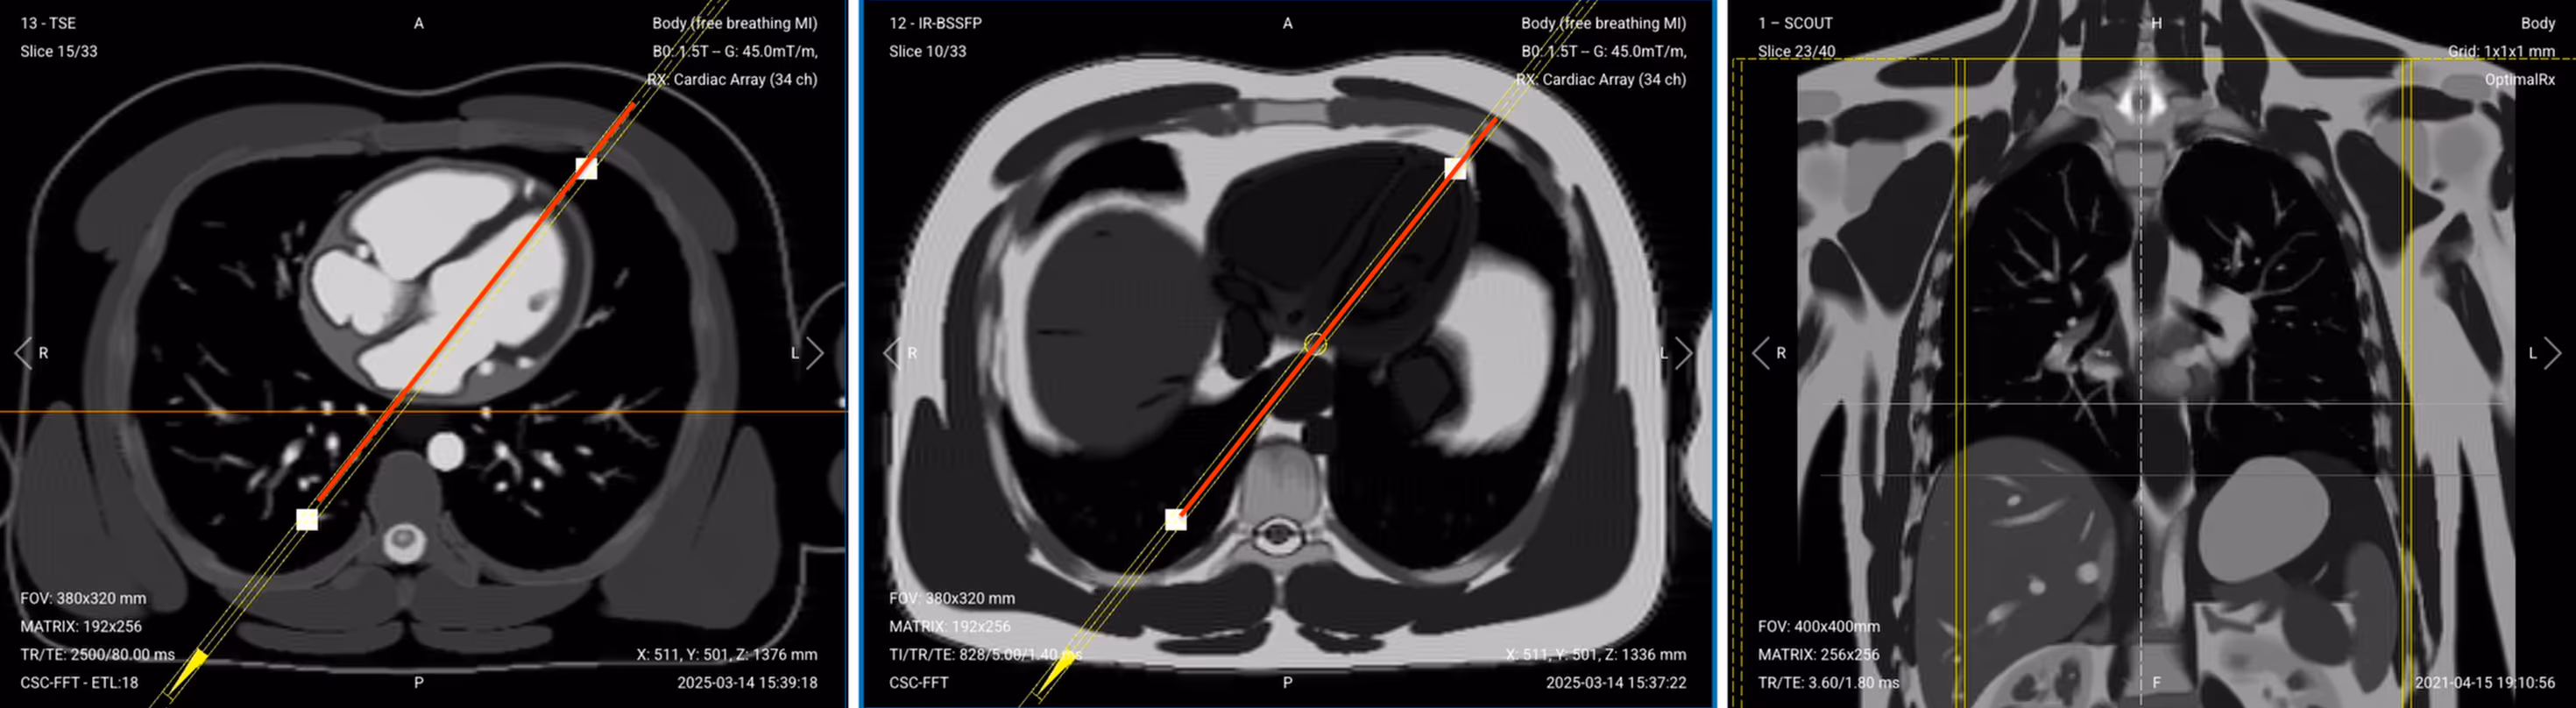

Once acquired, upload the initial localizer images into the three viewports.

Then, scroll through each of the image stacks to locate a central slice that clearly shows the anatomy of the heart.

✅ Correct Setup of Localizer Images for Cardiac Viability MRI: